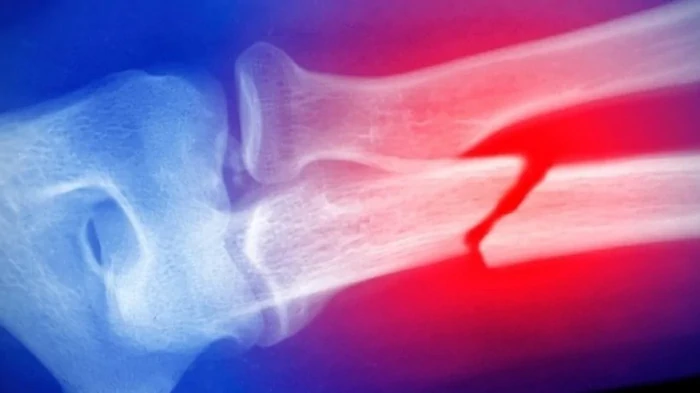

Сахарный диабет 2-го типа (СД2) поражает множество органов в нашем организме, приводя к серьезным и различным осложнениям, включая почечную недостаточность, сердечно-сосудистые заболевания, повреждение нервов и повышенный риск переломов. Недавнее исследование показало, что хотя люди с СД2 часто имеют более высокую минеральную плотность костной ткани (МПК), они, как ни парадоксально, подвержены большему риску переломов костей из-за ухудшения их качества, пишет News Medical. Исследование, опубликованное в журнале JAMA Network Open, в котором приняли участие 3008 женщин в возрасте от 75 до 80 лет, показало, что люди с СД2 имели более высокую МПК в тазобедренном суставе и поясничном отделе позвоночника. Однако микроархитектура их костей была слабее, что делало их более восприимчивыми к переломам. Вероятно, это необычное явление связано с такими факторами, как накопление конечных продуктов гликирования, снижение оборота костной ткани и изменение жировых отложений в костном мозге, которые негативно влияют на прочность костей. Помимо здоровья костей, исследование показало, что у женщин с СД2 заметно ухудшилась физическая функция. У них была слабее сила хвата, медленнее скорость ходьбы и им требовалось больше времени, чтобы начать движение, по сравнению с их сверстницами, не страдающими диабетом. Длительное лечение инсулином еще больше усугубляло эти физические недостатки, несмотря на более высокий уровень МПК, наблюдавшийся в этой группе. В исследовании также отмечается, что плохой гликемический контроль при СД2 повышает риск смертности и переломов, особенно переломов бедра. Женщины с самым высоким уровнем гликированного гемоглобина (HbA1C), что свидетельствует о плохом контроле уровня сахара в крови, имели значительно более высокий риск переломов, даже после поправки на другие факторы риска, такие как возраст и масса тела. Диабет оказывает значительное влияние на весь наш организм, причем осложнения выходят за рамки обмена глюкозы и включают ослабление структуры костей и ухудшение физической функции тела. Комплексное и своевременное лечение СД2 имеет решающее значение для снижения этих рисков и предотвращения прогрессирования осложнений со стороны различных пораженных органов. | |